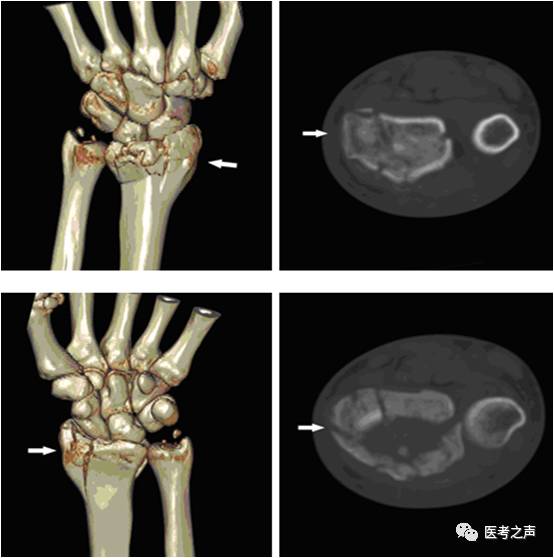

手部ct图片,手部ct

手部ct图片骨折